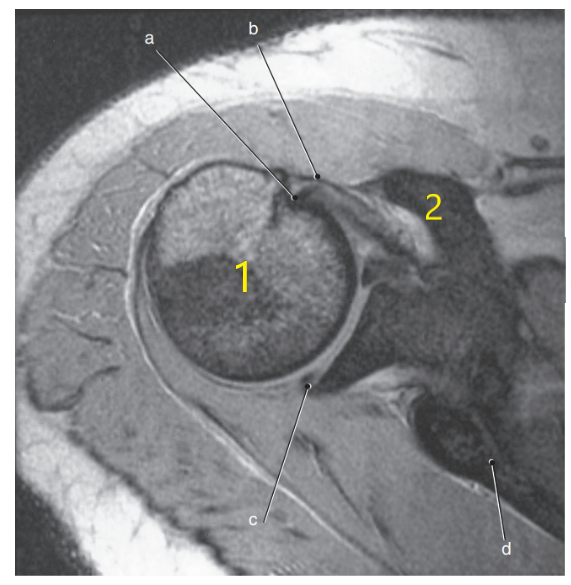

What anatomy is # 1 ?

Humeral head

What is letter c ?

Glenohumeral joint

Superior glenoid labrum

Posterior glenoid labrum

What is letter d ?

Triangular fibrocartilage complex

What is arrow # 3 ?

Teres minor tendon